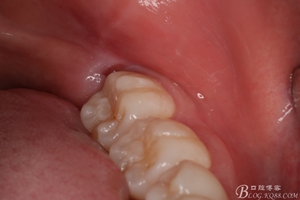

圖1.術(shù)前的口內(nèi)照片:38未萌出、牙齦輕度紅腫,37遠中有盲袋。